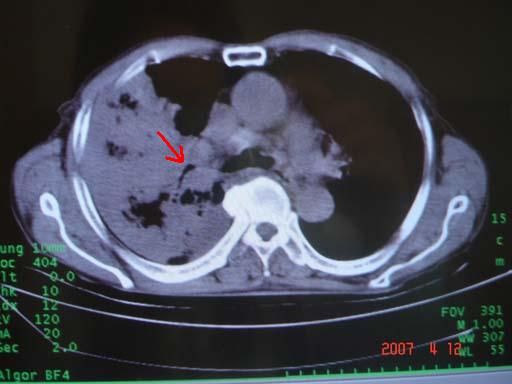

病灶局限在右肺中上叶,呈大片状实变影,内见空气支气管征,支气管分支较柔软,纵隔内未见肿大淋巴结.支持:感染性病变_1 大叶性肺炎.2 干酪性肺炎.

优先考虑右上肺干酪性肺炎并同侧中叶播散、胸腔积液。分析:右膈肌未见升高、纵隔未见明显右移,胸部各组淋巴结未见可疑肿大,中叶可见支气管铸形,肺野、肺门未见可确定肿块。

单从影像学上来看,该病人应首先考虑,右上肺感染(干酪性肺炎可能大)伴有右侧胸腔积液,理由如下:

1.病灶整体成宽基底征,而未见块状影

2.病灶内的透光区并不是含气支气管征,而像是坏死的肺组织后形成的

3.无肺不张的表现

4.纵隔那未见明显肿大淋巴结

结合病史,该病人尚需作进一步检查胸水,支气管镜,查痰等

有点象洗肉水的痰,其来源应当是实变引起的血细胞渗出导致,可见支气管气象,实变区有虫蚀状空洞,有明显胸腔积液,未见明显肺门区肿块影,考虑继发型肺结核,干酪性肺炎

右肺上叶实变,实变范围如此之大,如果用肺癌解释的化,应该是比较大的支气管开口发生完全阻塞,但观察上叶前后段支气管还是比较通畅,所以应考虑感染性病变,大叶性肺炎可能,建议抗炎治疗后复查。

考虑右中上叶大叶性肺炎,右侧胸水。抗炎治疗后复查。